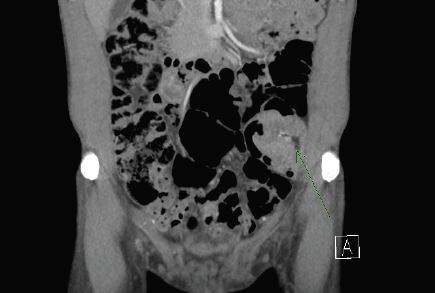

Intussusception is one of the common causes of intestinal obstruction in children, but it is a relatively rare condition in adults, accounting for only 1% to 3% of adult cases of intestinal obstruction. ...